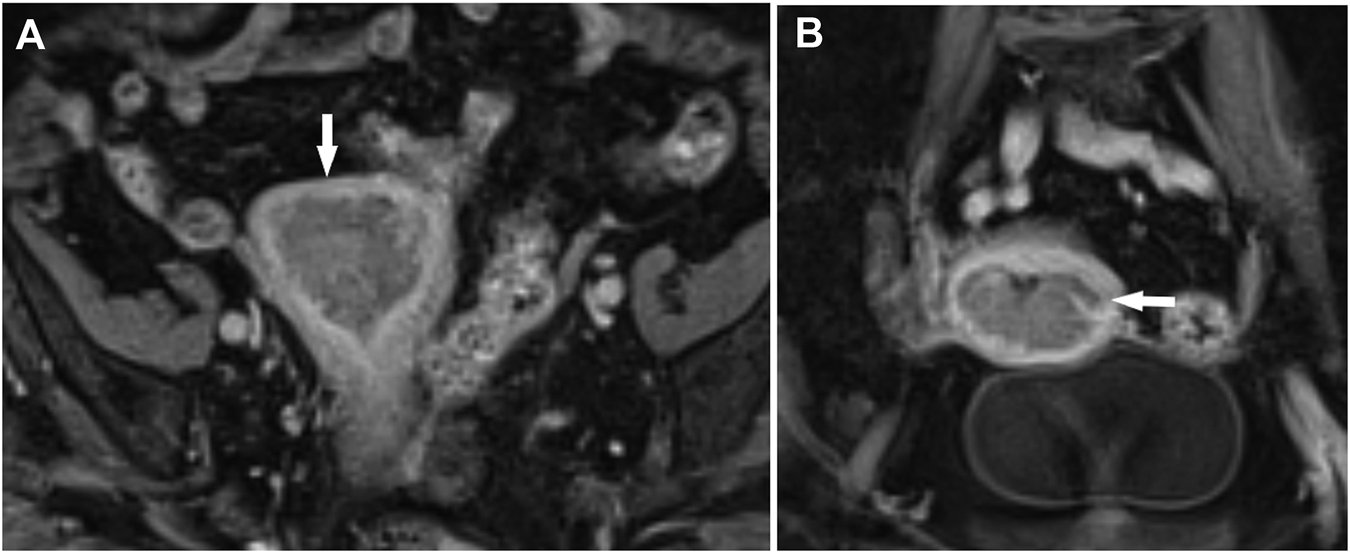

FIGURE 1

Endometrial cancer, stage T1b. Myometrial infiltration >50%. Post-contrast dynamic fat-sat T1 weighted VIBE image (fat-suppressed Volumetric interpolated breath-hold examination), (A) coronal view, (B) axial view.